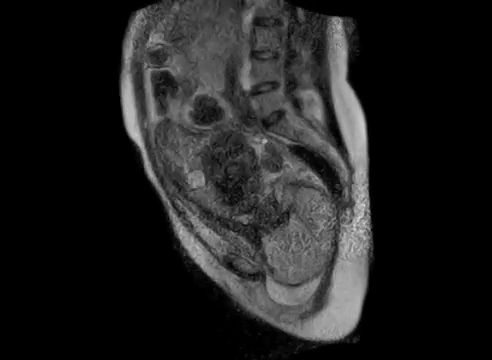

Echtzeit-Aufnahmen zeigen zum ersten Mal eine Geburt aus dem Inneren der Mutter. Der 30-Sekunden-Film aus dem Jahr 2010, der jetzt veröffentlicht wurde, zeigt die Wanderung des Babys durch den Geburtskanal einer 24-jährigen Mutter.